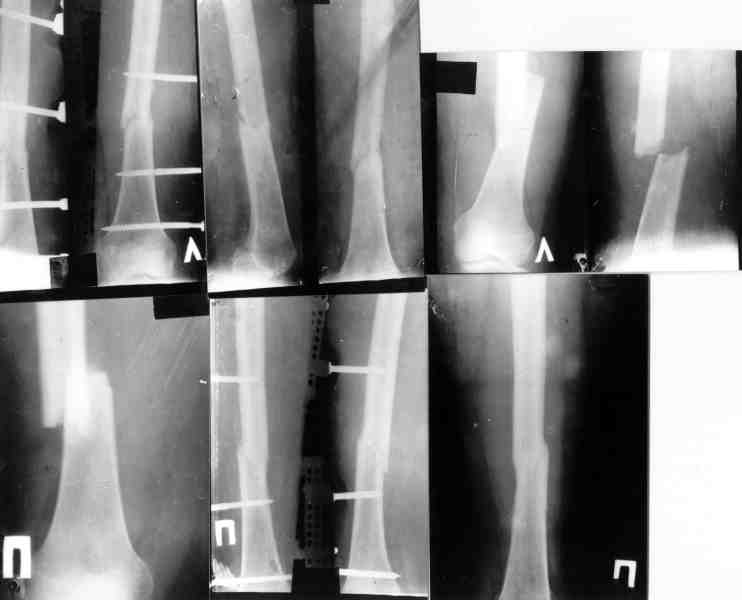

Re: Огнестрельный перелом плеча ( продолжение)

Вот еще информация, ознакамливайтесь pls/

Ув. коллега, а что такого нового или необычного в этих приложениях - стандартные методики. аппаратов внешней фиксации - море - этот просто один из них.